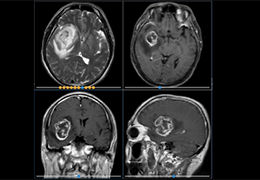

成像智能。

Eclipse 成像智能功能提供强大的处理能力和最佳质量的影像,同时减少质量错误并提高剂量效率。

凭借 AI、专有算法和先进的影像处理能力,提供出色的影像质量和无与伦比的诊断信心。